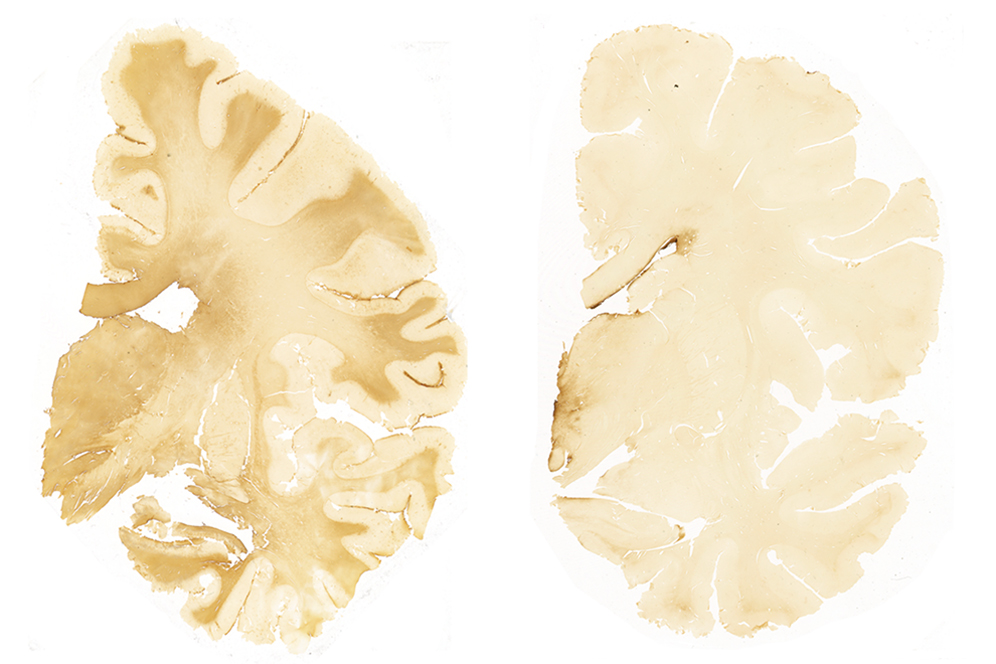

Brigham and Women’s Hospital Recognizes ECE Student for Research on CTE in Retired NFL Players

PhD Student Marcia Sahaya Louis Receives Research Excellence Award By Shereen Abubakr (QST '18) Electrical and Computer Engineering PhD student Marcia Sahaya Louis (ECE ‘21) received a... More

BU-Led Study May Explain CTE without Concussions

A new BU-led study published Thursday in the journal Brain suggests that chronic traumatic encephalopathy (CTE) is caused by head injuries, not by concussions. The research explains why 20 percent of athletes who exhibited the early stages of the progressive brain illness postmortem never had a diagnosed concussion. More